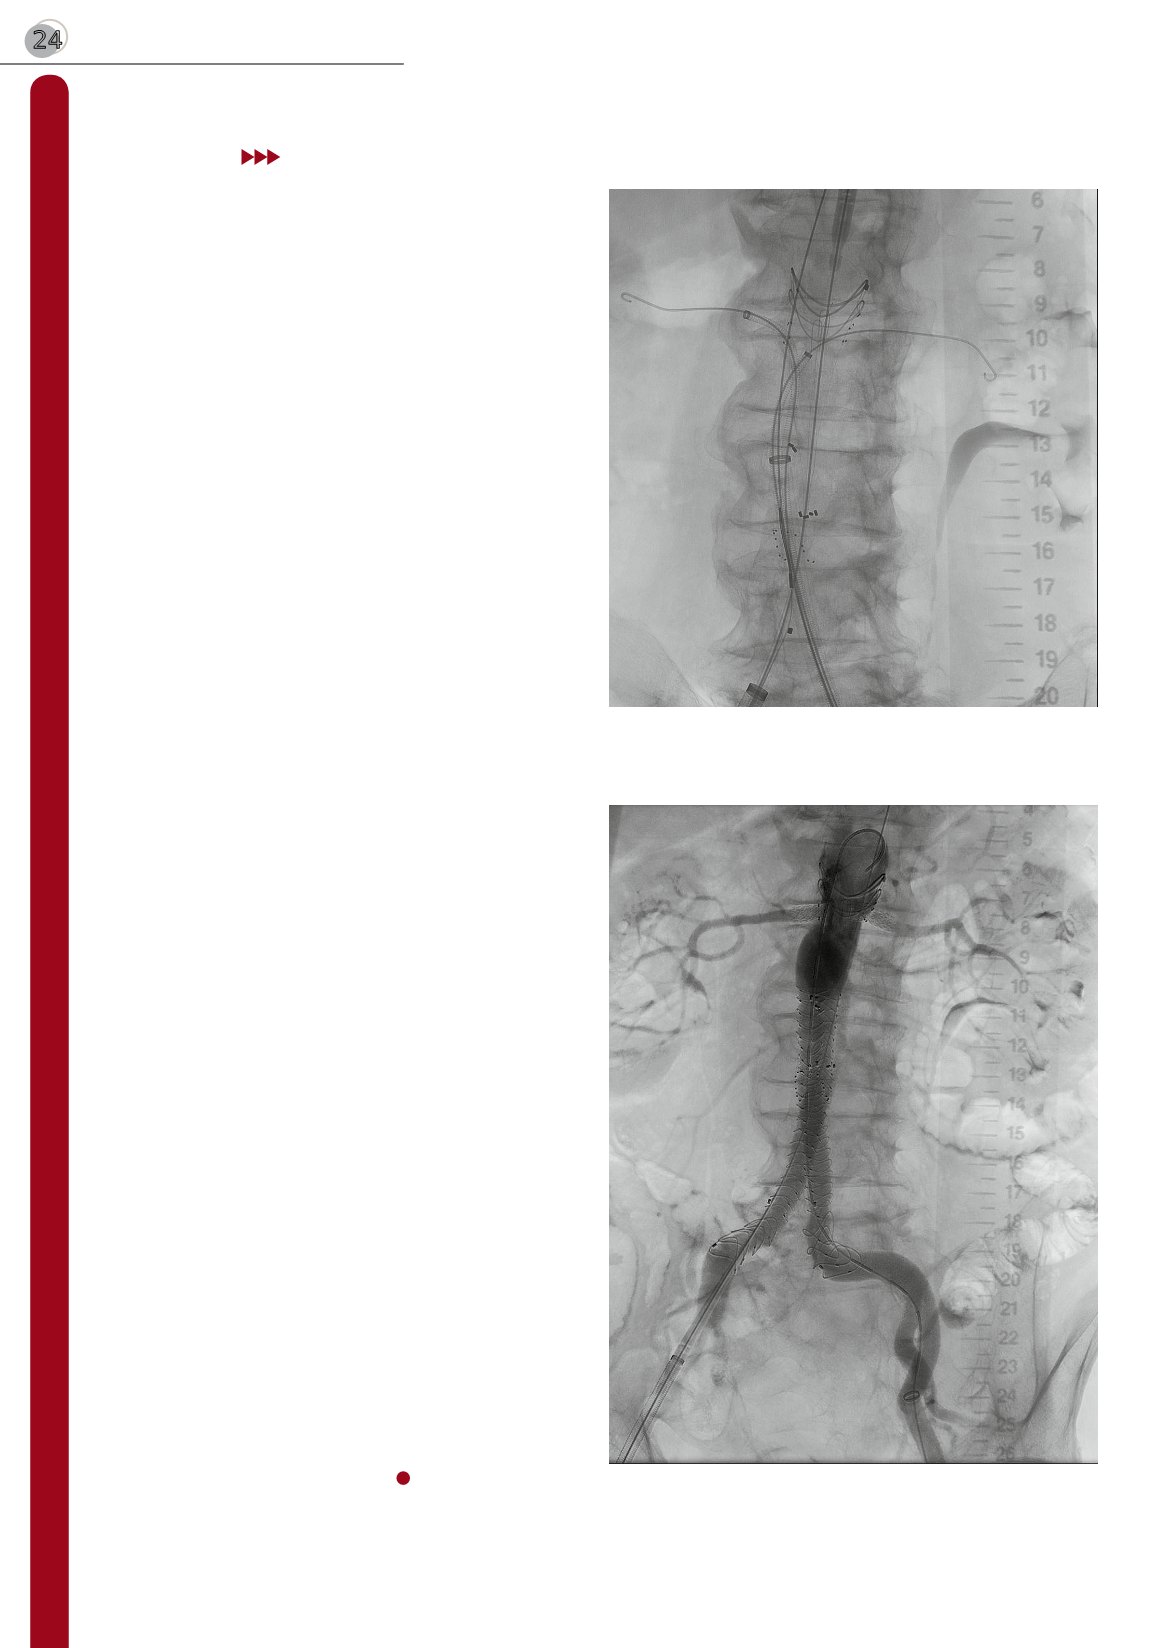

Obraz nr 3: Zdjęcia śródoperacyjne stentgraft fenestrowany

arteriografgia pooperacyjna. Widoczny przepływ kontrastu przez

stentgraft fenestrowany Anaconda i stenty w tętnicach nerkowych.

Tętniak aorty brzusznej wyłączony z krążenia.

Obraz nr 2: Zdjęcia śródoperacyjne – stentgraft fenestrowany. Wi-

doczny stentgraft fenestrowany Anaconda i prowadniki w tętnicach

nerkowych przygotowane do implantacji stentów.